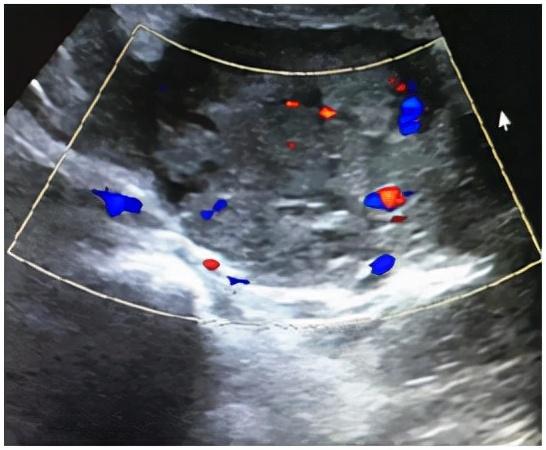

2020年11月9日上午,年轻患者王XX走进晋安区妇幼保健院妇科门诊。停经两个多月后,她间歇性阴道出血20多天。她来看医生是因为阴道出血增加并伴有左下腹痛。b超显示:妊娠早期,宫腔积血,左阑尾区不均匀回声(51*37*46mm),盆腔积液。血清HCG 125417.00 iu/mL,孕酮30.20ng/mL。询问详细病史,患者今年怀孕半年,9月中旬在另一家医院接受促排卵治疗。结合病史和辅助检查,快速判断:左侧阑尾区肿块是什么?是不是又一个宝宝走错地方了,也就是我们常说的宫外孕?还是怀孕期间,卵巢内分泌激素的黄体破裂出血了?

这两种可能性都可能随时危及大出血患者的生命,影响宫内妊娠的发展。因此,对妇科住院患者应立即治疗,密切观察患者生命体征。11.10上午,王女士再次出现持续性严重左下腹痛。b超复查显示妊娠早期,宫腔积血,左阑尾区回声不均(64*49*40mm),盆腔积液。与入院患者相比,肿块明显变大,患者疼痛明显加重。考虑到盆腔持续出血,需立即行腹腔镜探查。在向患者及其家属说明病情和风险后,在全身麻醉下进行紧急腹腔镜探查。术中盆腔积血约300ml,左输卵管腹部及伞端增厚约3*4cm,伞端有活动性出血。术中再次医患沟通后切除了大部分左侧输卵管。通过切片标本,我们可以看到有组织的绒毛组织。术后继续给予药物流产等对症治疗。

有生育要求,特别是辅助生育治疗后的患者,要尽量保证宝宝在宫内不受影响,早诊断早治疗至关重要。阴道超声是目前诊断HP的最好手段。